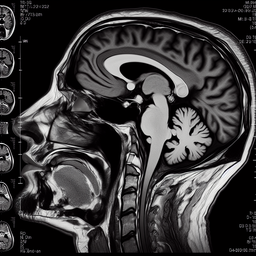

Магнітно-резонансна томографія (МРТ) скронево-нижньощелепного суглоба (СНЩС) — це неінвазивний метод діагностики, який дозволяє отримати детальні зображення суглоба. Це дослідження допомагає у виявленні патологій, таких як запалення, артрит, дислокація диска чи інші структурні аномалії.

3. **Інформативність**: МРТ дозволяє оцінити як кісткові, так і м'якотканинні структури суглоба.